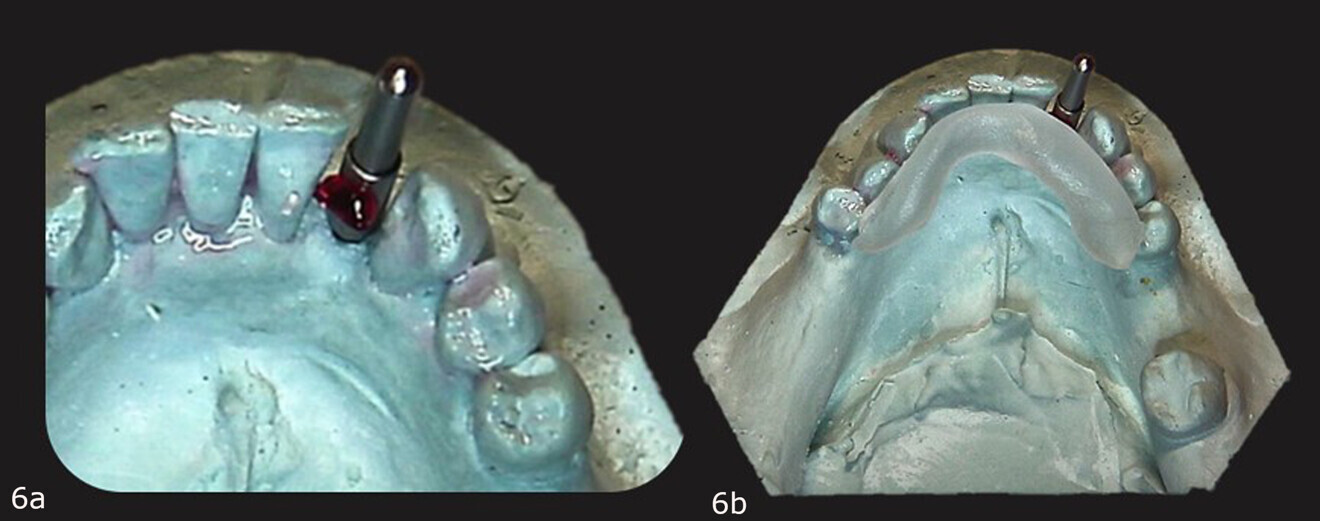

Figs. 6a & b: Primopattern LC Gel placed over the cleat (a). Primosplint placed on the lingual aspect of the teeth on the cast (b).